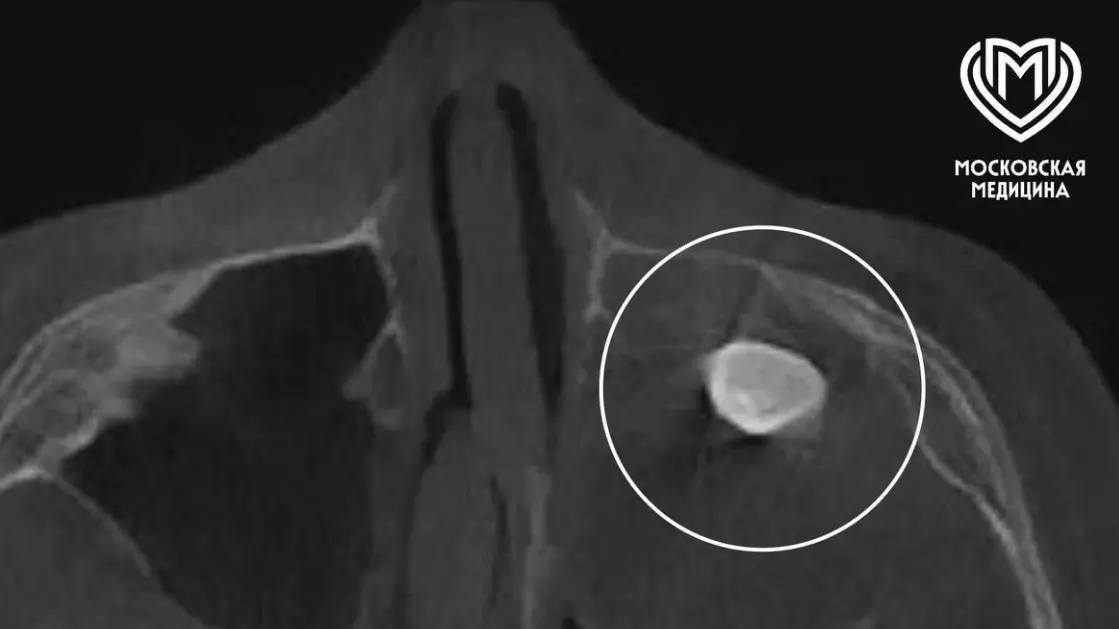

Юный пациент почувствовал дискомфорт из-за заложенности носа и асимметричной формы лица, поэтому семья обратилась за помощью. В одной из частных клиник врачи выявили наличие необычного зуба в гайморовой пазухе, но родители мальчика приняли решение получить дополнительное мнение от профильных экспертов Филатовской детской больницы. Коллектив медицинского учреждения провёл тщательное обследование, чтобы точно определить объем и сложность предстоявшего вмешательства.

Врачи собрали консилиум, результатом которого стало решение о необходимости операции по Колдуэллу-Люку. Исключительный опыт и слаженные действия хирургов позволили успешно провести деликатную процедуру — во время хирургического вмешательства специалисты обнаружили новообразование, внутри которого и был обнаружен образовавшийся зуб. Благодаря профессионализму и внимательному подходу медиков, проблема мальчика была полностью решена, а восстановление проходит успешно.